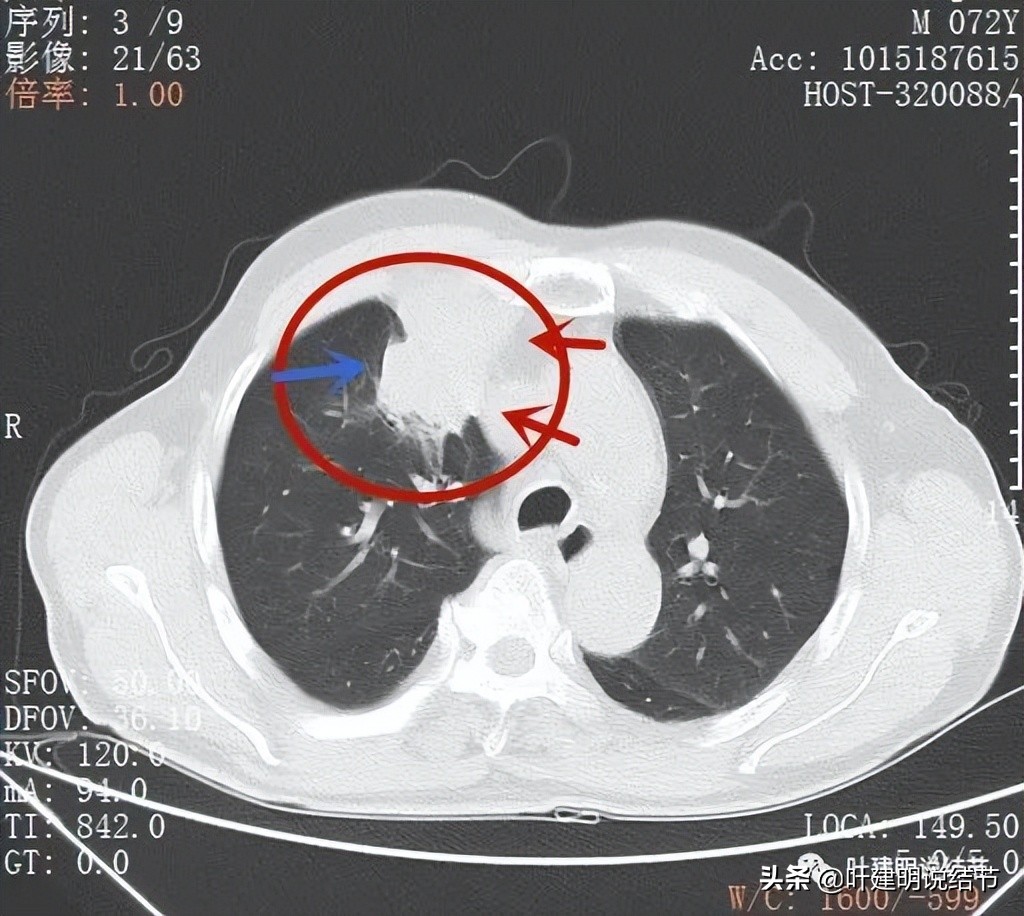

病灶巨大,边缘较平滑

因为肿块巨大,整体看有些层面还是有鼓鼓的感觉的(红色箭头),但仍边缘过于光滑(蓝色箭头)